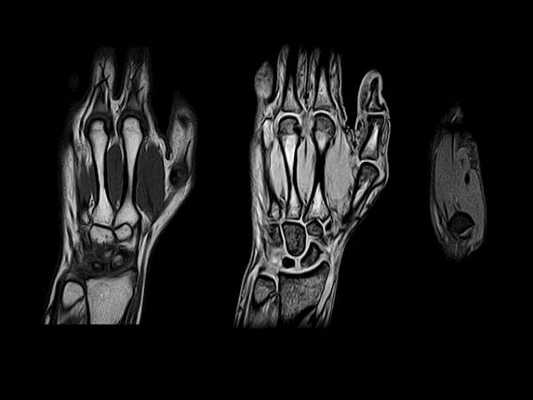

Некоторые костные переломы запястья также трудно увидеть при рентгенографии или даже КТ. Это особенно относится к трабекулярным переломам, типичным для спортивной травмы.

МРТ кисти. Корональная Т1-взвешенная и Т2-взвешенная МРТ. Трабекулярный перелом лучевой кости без смещения.

МРТ кисти. Корональные Т1- и Т2-взвешенные МРТ. Повреждение задней группы связок.

Очень сложны в диагностике переломы ладьевидной кости - они часто пропускаются на рентгенограммах. Осложнением такого перелома может стать асептический ее некроз. На Т2-взвешенных МРТ при переломах виден отек костного мозга, обычно частично охватывающий кость.

МРТ кисти. Т1-взвешенная корональная МРТ. Асептический некроз ладьевидной кости.

На асептический некроз (болезнь Кинбека, Kienböck) очень похож синдром локтевого вклинения, когда ладьевидная кость вклинивается в локтевую. МРТ мелких суставов кисти обсуждается в отдельной статье.